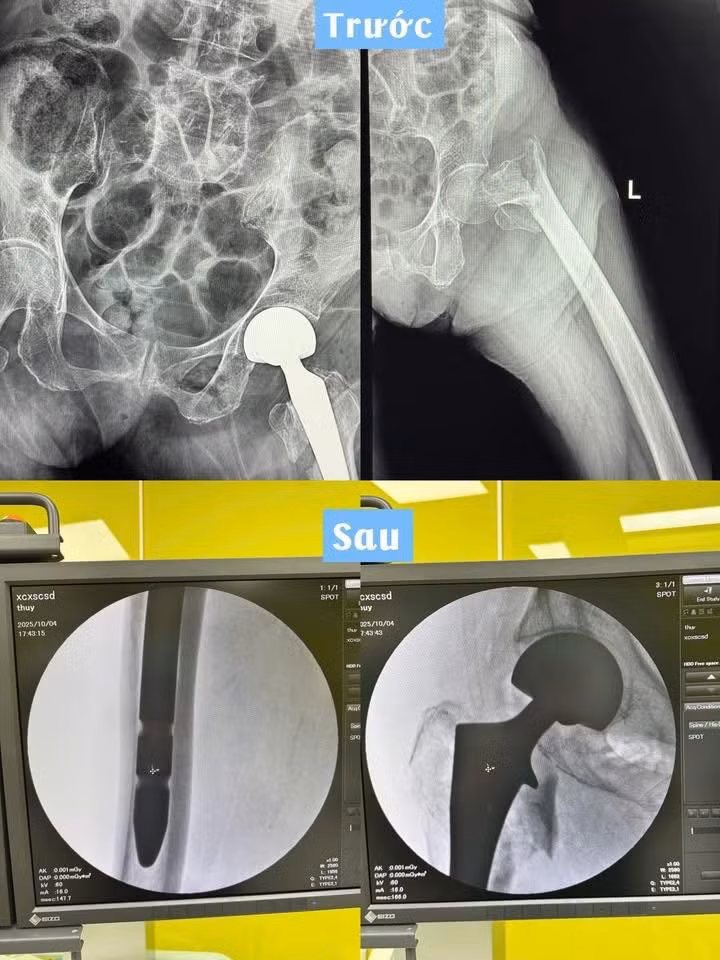

Hình ảnh xương đùi của bệnh nhân trước và sau phẫu thuật - Ảnh BVCC

Các bác sĩ đã tiến hành thay khớp háng bán phần chuôi dài, một kỹ thuật đòi hỏi độ chính xác cao, đặc biệt ở người bệnh tuổi cao và có xương yếu.

Theo bệnh viện, ca phẫu thuật được tiến hành trong điều kiện vô khuẩn tuyệt đối, với sự phối hợp chặt chẽ giữa các chuyên khoa. Nhờ chuyên môn vững vàng, trang thiết bị hiện đại và quy trình gây mê hồi sức an toàn, ca mổ diễn ra thuận lợi và thành công. Sau mổ, cụ bà tỉnh táo, các chỉ số sinh tồn ổn định, hiện đang tập vận động nhẹ tại khoa.